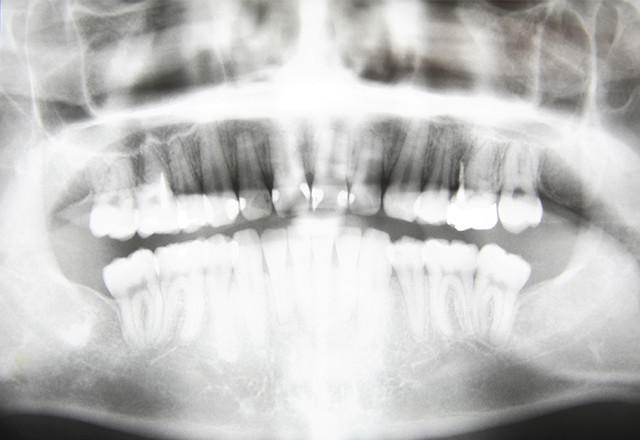

- 的確な診断を行うために、レントゲンを撮影します。